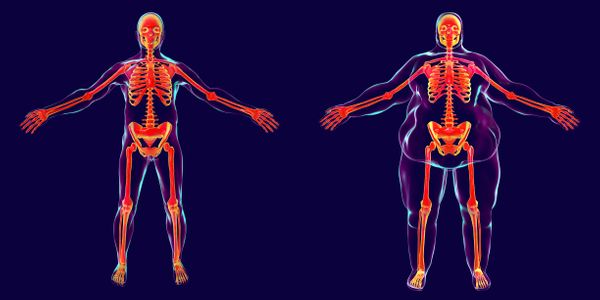

Eine der Folgen von Adipositas ist die enorme Belastung der Knochen.